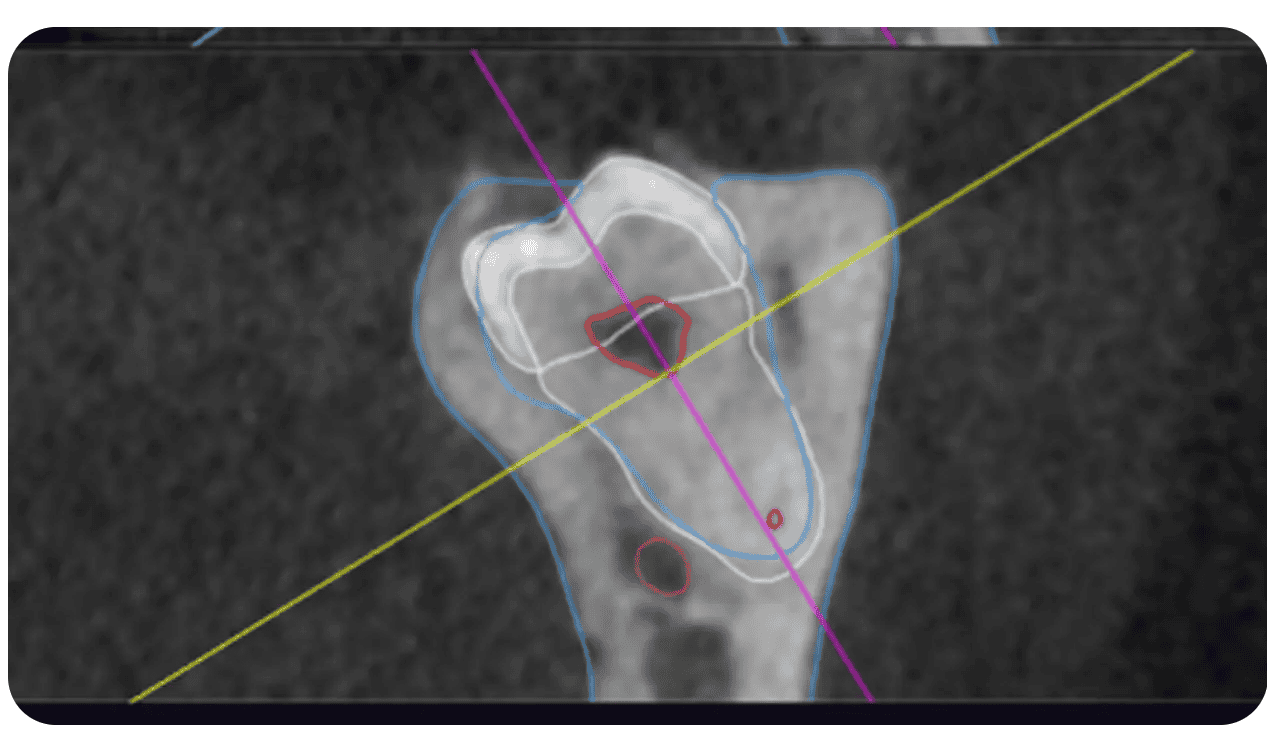

Raportul Modelului 3D de inteligență artificială include un mod de reconstrucție în mai multe planuri. Secțiunile sunt poziționate în funcție de obiectul selectat în vizualizarea 3D și prezintă contururi colorate ale structurilor segmentate.

Contururi colorate ale structurilor segmentate în reconstrucția multiplanară (MPR)

Trasarea automată a canalului mandibular